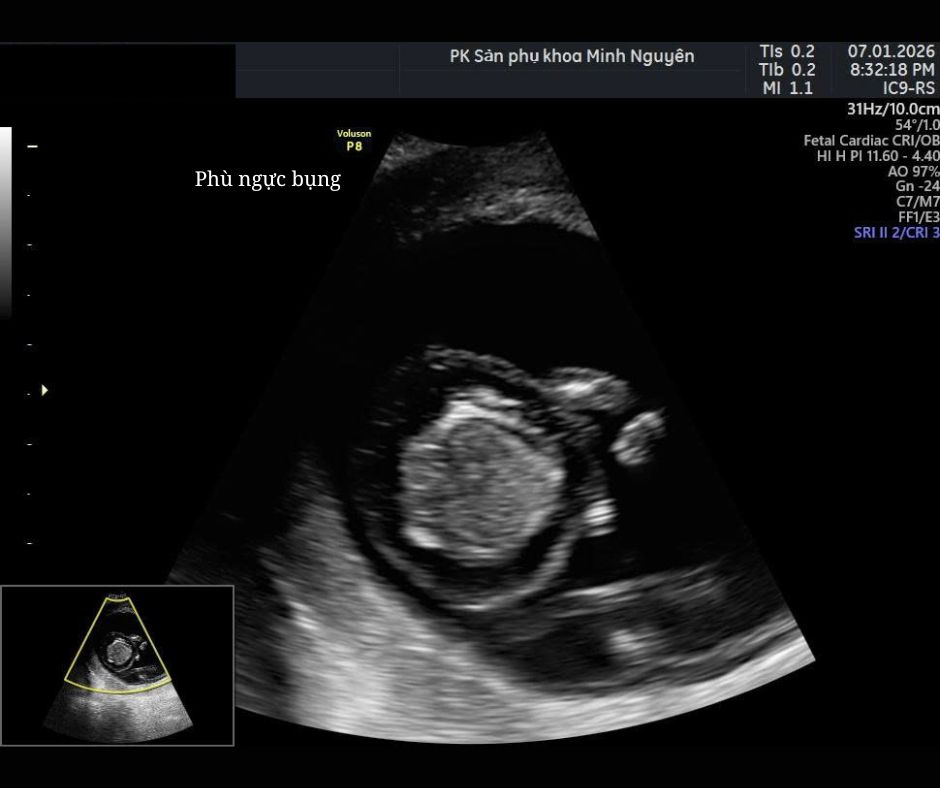

Phù thai (Hydrops fetalis) là tình trạng ứ dịch bất thường trong cơ thể thai nhi, được xác định khi siêu âm thấy dịch tích tụ ở từ hai khoang trở lên, ví dụ:

- Ổ bụng (cổ trướng)

- Khoang màng phổi

- Khoang màng tim

- Phù da toàn thân

Dấu hiệu phù thai trên siêu âm thường gặp

Một thai được nghi ngờ phù khi xuất hiện ít nhất hai trong các dấu hiệu sau:

1. Cổ trướng (Ascites)

Dịch tự do trong ổ bụng, thường là dấu hiệu sớm.

2. Tràn dịch màng phổi

Dịch bao quanh phổi, có thể một bên hoặc hai bên.

3. Tràn dịch màng tim

Lớp dịch mỏng bao quanh tim dày bất thường.

4. Phù da toàn thân

Da thai dày lên, đặc biệt vùng bụng và lưng.